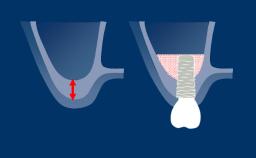

Successful implant treatment requires a prosthodontically driven implant plan to determine the ideal implant position. The implant position should facilitate the placement of an optimal definitive prosthesis which fulfils both functional and esthetic demands and mimics the natural dentition.

By using additional diagnostic investigations, site-specific surgical and prosthodontic requirements can be identified and assessed. This helps to minimize the risk of complications and failures following implant treatment.